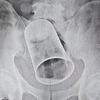

Um homem foi parar na emergência após ter fortes dores abdominais. Foi constatado, por meio de raio-x, que o corpo estranho se tratava de um tubo de desodorante. O objeto estava retido no ânus há três semanas. Ele teve que passar por cirurgia e o procedimento durou 2 horas.  O caso aconteceu em West Bengal, na Índia.

O paciente de 27 anos, com o nome não revelado, teve dano no esôfago e intestino. Ele ficou hospitalizado e não foi capaz de evacuar durante este período. De acordo com a equipe médica, em entrevista ao canal de notícias India’s News18, ele corria risco de vida se não retirasse o objeto do corpo.

Mesmo com a cirurgia, o paciente não se recuperou totalmente. O homem deve passar por outros procedimentos para reparar a situação.